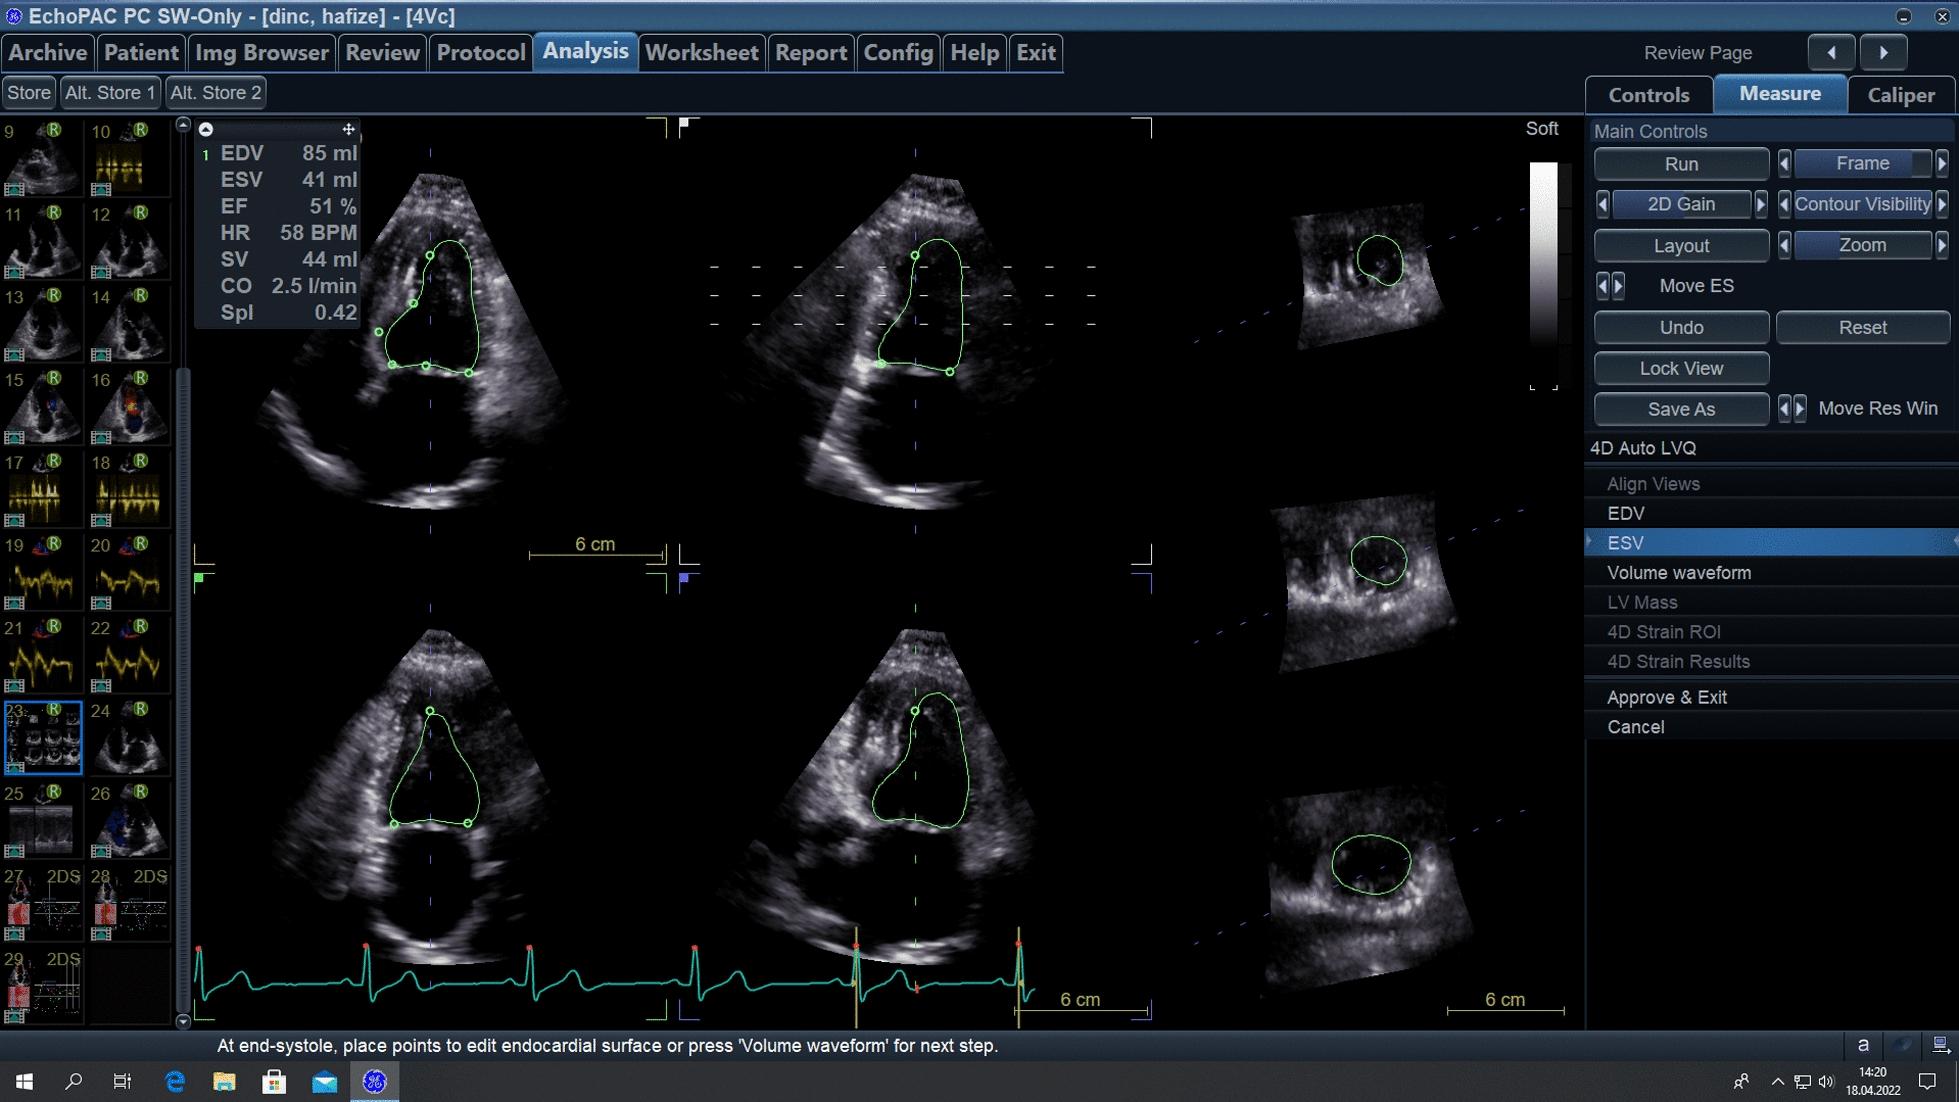

Graft choices other than left anterior descending artery (LAD)-internal thoracic artery (ITA) anastomosis in coronary artery bypass grafting (CABG) surgery are still controversial. Although 2-dimensional transthoracic echocardiography (2D TTE) is still the most commonly used method, more is needed to diagnose myocardial dysfunction. Ventricular strain values obtained by speckle tracking echocardiography (STE) or tissue Doppler imaging (TDI) methods can much better detect subclinical changes. This study aims to detect early postoperative myocardial function changes compared to single ITA/Bilateral Internal Thoracic Artery (BITA) use by measuring 3-dimensional ejection fraction (3D EF) and ventricular strain values and comparing them according to graft preference.

METHODS

The study included 35 isolated CABG patients. All patients underwent on-pump CABG via sternotomy. The patients were divided into two groups using single ITA and BITA. Preoperative and postoperative 1st-week 3D EF and ventricular strain values of the patients were calculated using semi-automatic software. The recorded data were compared and evaluated between the two groups.

RESULTS

Of The 35 patients participating in the study, 74.3% (n = 26) were male, 25.7% (n = 9) were female, and their average age was 62.7 ± 7.9 years. Preoperative 3D EF values of the patients were 54.4 ± 8.3% and postoperative 49.5 ± 8.2%. The mean preoperative Apical Long Axis Longitudinal Strain (APLAX LS) was calculated as - 16.2 ± 5.0%, 4 Chambers Longitudinal Strain (4CH LS)-16.8 ± 4.6%, 2 Chambers Longitudinal Strain (2CH LS) - 17.0 ± 4.9%, and Global Longitudinal Ventricular Strain (GLVS) - 16.7 ± 4.2%. Postoperative strain values were measured as - 15.1 ± 4.8%, - 14.7 ± 4.9%, - 14.6 ± 5.6% and - 14.8 ± 4.6%, respectively. When the groups were evaluated within themselves, the mean preoperative 3D EF of the patients in the single ITA group was 52.5 ± 8.8%, while the postoperative mean was 47.7 ± 6.0%. In the BITA group, preoperative 3D EF was 56.3 ± 7.5 and postoperative 51.4 ± 9.8. A decrease in strain values was detected in all groups except APLAX planes.

在冠状动脉旁路移植术(CABG)中,除左前降支(LAD)-内乳动脉(ITA)吻合术以外的移植物选择仍存在争议。尽管二维经胸超声心动图(2D TTE)仍然是最常用的方法,但仍需要更多的方法来诊断心肌功能障碍。斑点追踪超声心动图(STE)或组织多普勒成像(TDI)方法获得的心室应变值可以更好地检测亚临床变化。本研究旨在通过测量 3 维射血分数(3D EF)和心室应变值来检测与单一 ITA/双侧内乳动脉(BITA)使用相比的术后早期心肌功能变化,并根据移植物选择进行比较。

方法

该研究纳入了 35 例孤立性 CABG 患者。所有患者均通过胸骨切开术进行体外循环下 CABG。根据使用的 ITA 和 BITA 将患者分为两组。使用半自动软件计算患者术前和术后第 1 周的 3D EF 和心室应变值。比较两组之间的记录数据。

结果

35 例参与研究的患者中,74.3%(n=26)为男性,25.7%(n=9)为女性,平均年龄为 62.7±7.9 岁。患者术前 3D EF 值为 54.4±8.3%,术后为 49.5±8.2%。术前平均心尖长轴纵向应变(APLAX LS)为-16.2±5.0%,4 腔室纵向应变(4CH LS)为-16.8±4.6%,2 腔室纵向应变(2CH LS)为-17.0±4.9%,整体纵向心室应变(GLVS)为-16.7±4.2%。术后应变值分别测量为-15.1±4.8%、-14.7±4.9%、-14.6±5.6%和-14.8±4.6%。当在自身组内进行评估时,单一 ITA 组患者的术前平均 3D EF 为 52.5±8.8%,而术后平均为 47.7±6.0%。在 BITA 组中,术前 3D EF 为 56.3±7.5,术后为 51.4±9.8。所有组除 APLAX 平面外,均检测到应变值下降。